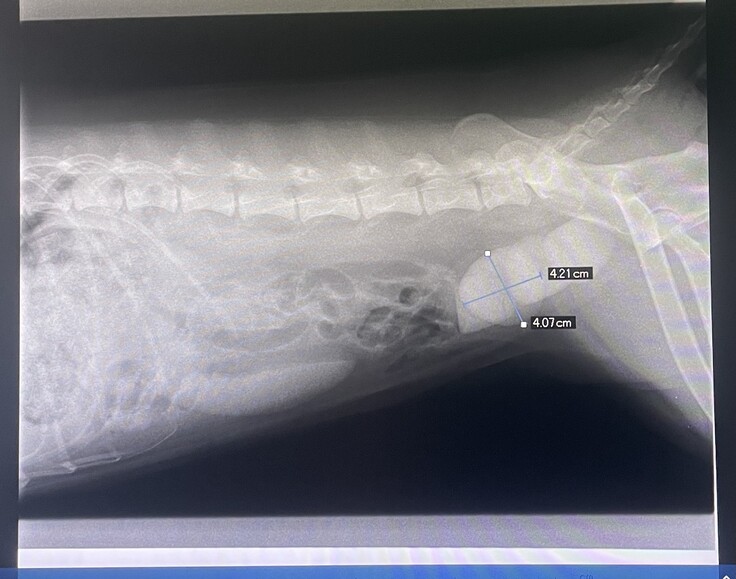

あまりにも状態がひどいので、レントゲンを撮ってもらうと、

4センチ大の巨大な結石が4つもあり膀胱がパンパンの状態でした・・・!!

まだ6歳ということ、

この大きさだと療法食で溶かすことも難しいこと、

結石があることで菌が繁殖しやすく、出血しているから、他の臓器へ影響する可能性もないとはいいきれないこともあり、手術を提案されました。

手術中の写真も見せて頂きましたが、4つの大きな結石が、膀胱に隙間がなく埋め尽くされていました。

1/23 A病院(診察・尿検査・超音波・レントゲン):9,570円